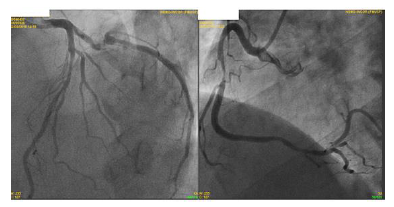

Paciente do sexo feminino, 65 anos, com antecedente de hipertensão arterial, tabagismo, diabética e com histórico familiar de doença arterial coronariana. Vem em consulta ambulatorial com histórico de angina de início há 6 meses, atualmente aos moderados esforços, CCS II (Canadian Cardiovascular Society), sem dispneia ou demais queixas. Em uso ambulatorial de aspirina 100mg ao dia, atorvastatina 40mg ao dia, metformina 850mg 3x ao dia, enalapril 20mg 2x ao dia e anlodipino 10mg ao dia. Exames laboratoriais revelam: LDL colesterol de 88 mg/dl, HDL colesterol de 51 mg/dl, triglicérides de 177 mg/dl, glicemia de jejum de 140 mg/dl e hemoglobina glicada de 7,4%. Ao exame físico, Pressão arterial de 150/70 mmHg, frequência cardíaca de 79 batimentos por minuto. Demais sem alterações.

Durante a investigação, a paciente apresentou piora da angina, atualmente em CCS III e manteve-se refratária às medicações. Realizou o cateterismo (imagem abaixo).

I. Paciente apresenta lesão grave em artéria coronária direita e a revascularização percutânea dessa lesão pode ser realizada visando melhora de sintomas.

II. Paciente apresenta lesão em artéria coronária descendente anterior. O uso de métodos fisiológicos, como reserva de fluxo coronário (FFR) pode ser indicado para melhor avaliação e caso FFR menor que 0,8 a revascularização está indicado.

III. Em situações de lesões triarteriais, com acometimento de coronária descendente anterior (DA) em porção proximal, há indicação de revascularização. Deve-se calcular o Synthax escore e caso ele for maior que 32, há indicação de revascularização percutânea (via hemodinâmica) e caso menor que 32, há indicação de revascularização cirúrgica.

IV. Independente do tipo de revascularização a ser indicada (percutânea ou cirúrgica), o paciente deve receber dupla antiagregação plaquetária por 1 ano, com indicação Classe IA de diretrizes.

Assinale a alternativa correta.